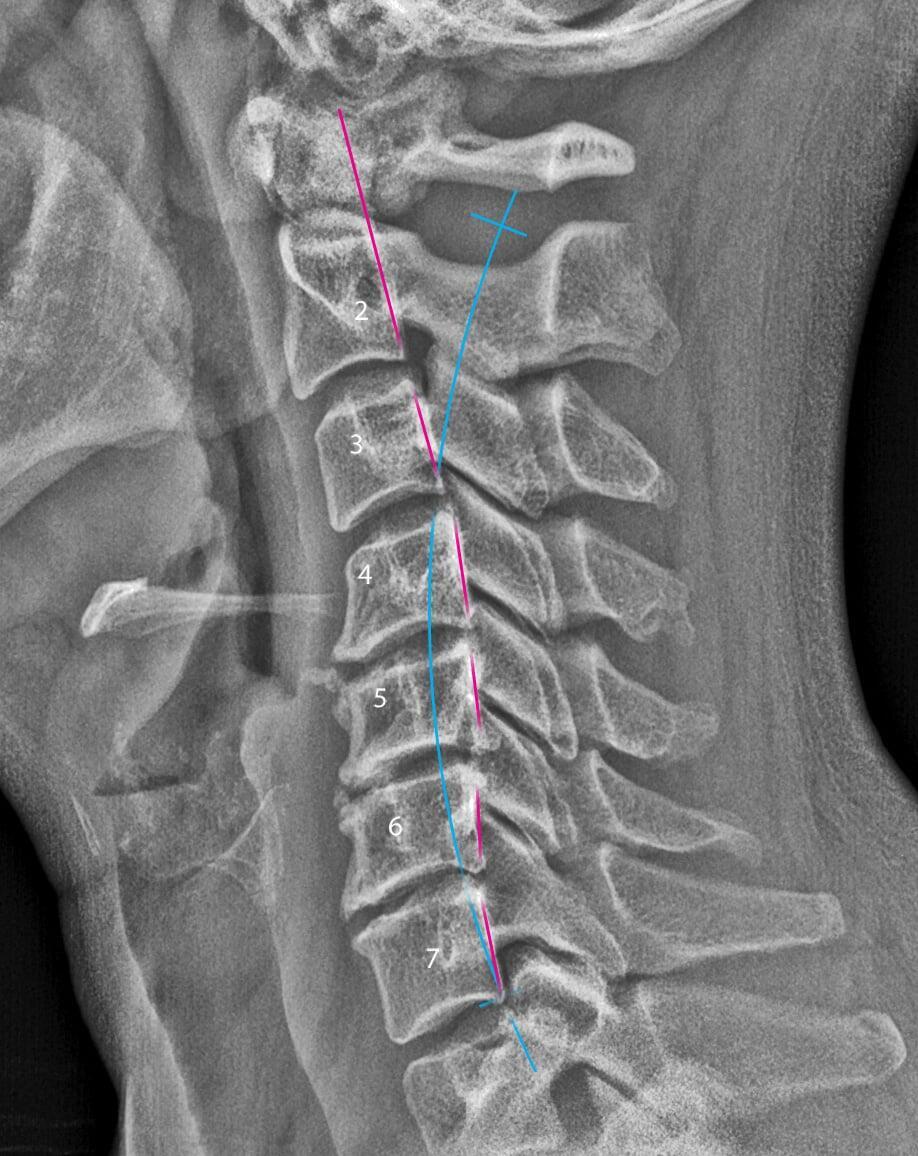

Optimal health can start with proper posture and efficient signaling between your brain and body. Subluxations can prematurely age the spine and interfere with the communication between your brain and body. Poor function and healing can be the result.

WHAT ARE SUBLUXATIONS?

A subluxation is a misalignment of the spine affecting biomechanical and neurological function.